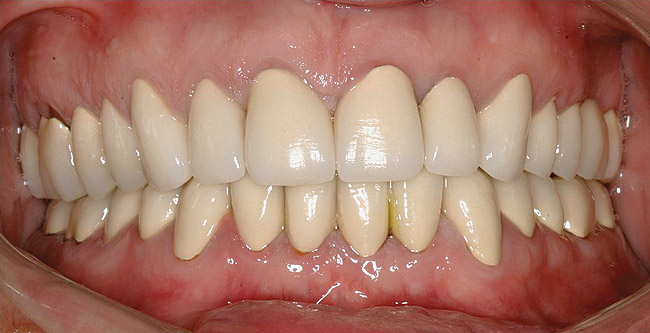

Figure  14  Full-mouth rehabilitation with porcelain-fused-to-metal.

Figure 14